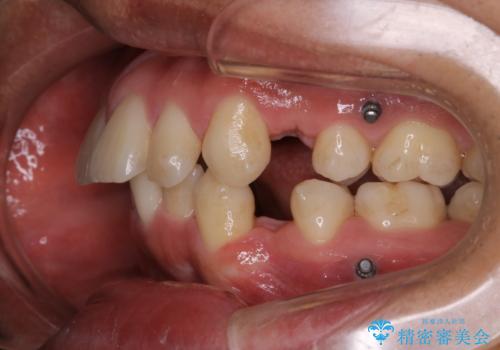

矯正中は汚れが付きやすいため、着色がとても多く付いていました。

抜歯したスペースや装置の周りの磨き方などとても難しため、定期的にクリーニングをおすすめします。